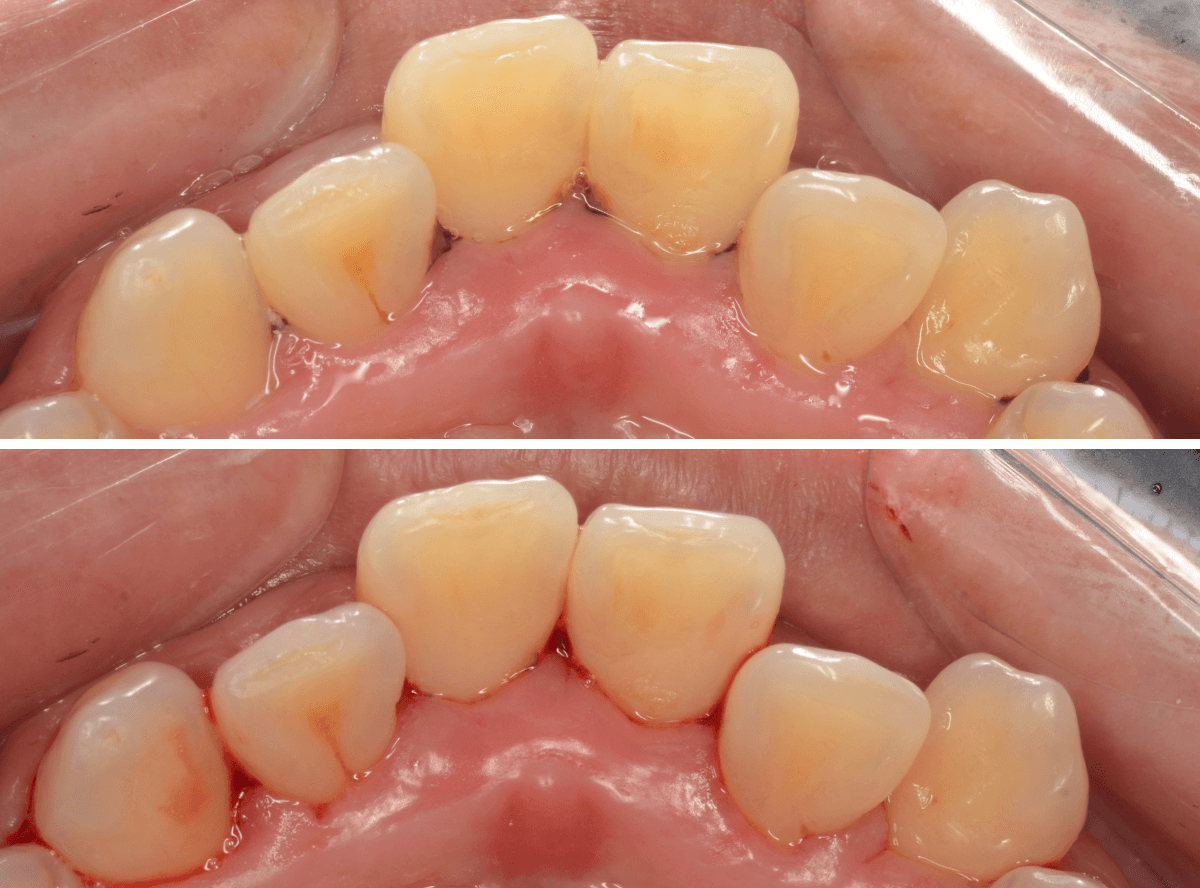

Case.3 縁下歯石除去後、3か月の状況

今回は、下の前歯の縁下歯石を除去した後、3か月後のメンテナンスにいらっしゃった方の治療前後です。

前側から見た所です。

とても綺麗に歯肉が治っているのがわかると思います。

歯石除去が終わったあとも、頑張ってお手入れしているのがうかがえます。

歯石除去だけでは、ここまで綺麗には治りません。

裏側の歯肉の状態も大きく変わりました。

年齢もお若い方なので、歯肉の回復も早いです。

ある程度まで歯周病が進行してしまいますと、完全に歯肉が元に戻るのは難しくなってしまいます。

本格的な歯周病になる前に治療を受けていただけて、本当に良かったと思います。

あとは、油断せずに持続していただきたいと思っています。